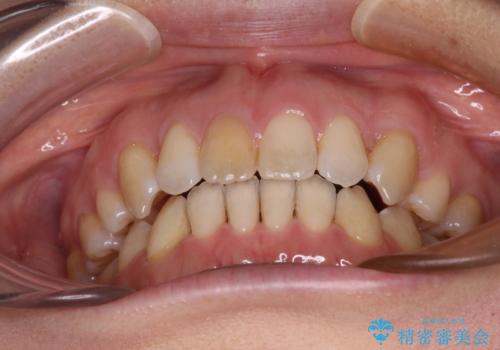

- 上の前歯の飛び出した感じを改善したいとのことで来院された患者様です。

上顎左右第一小臼歯2本、下顎左右第二小臼歯2本を抜歯し、ワイヤー装置にて口元を引っ込めるよう矯正治療を行うこととしました。

上下の前歯に隙間が空くほど上顎前歯が前に飛び出していましたが、抜歯矯正により上下前歯がぴったりと付くほど口元を引っ込めることができました。